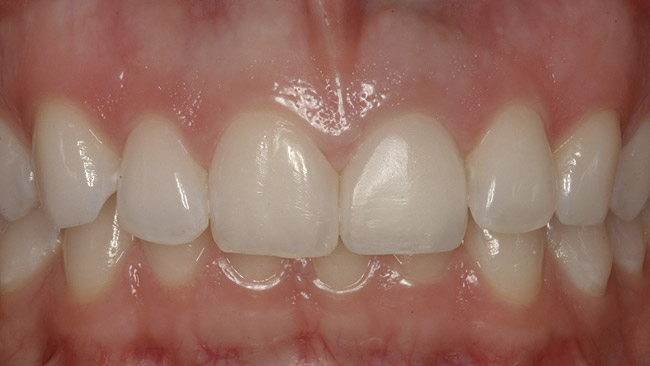

The final screw-retained crown was delivered and torqued onto the implant to 35 Ncm; the restorative dentist then sealed the screw access with a cotton pellet and composite (Figure 20 and Figure 21). Various views of the final crown are shown in Figure 22 through Figure 25, including a full-face photograph.

The gingival frame of the final implant crown on tooth No. 9 successfully matched that of natural tooth No. 8 (Figure 23). Accomplishing this required not only preservation of the existing free-margin height, but also the mirroring of the zenith point (at the approximate junction of the middle and distal thirds of each incisor’s clinical crown).

Kinsel and Capoferri (restorative dentist and laboratory technician, respectively) emphasize maintaining the zenith with a harmonious FGM around implant crowns and adjacent teeth. They highlight the importance of provisional restoration contouring by the restorative dentist, and skillful modification of the master cast by the laboratory technician to emulate natural cementoenamel junction anatomy, whose convexity dictates the gingival frame.36 The provisional bis-acryl crown designed and fabricated by this patient’s restorative dentist enabled this elusive esthetic goal by introducing a slightly convex subgingival contour, establishing a lifelike emergence profile that was ultimately maintained in the definitive restoration (Figure 24).

Figure 20  Screw-retained zirconia crown, customized zirconia stock abutment (one-piece restoration), site No. 9—final periapical view.

Figure 20

Figure 22  Final zirconia crown, No. 9, in occlusion—facial view.

Figure 22